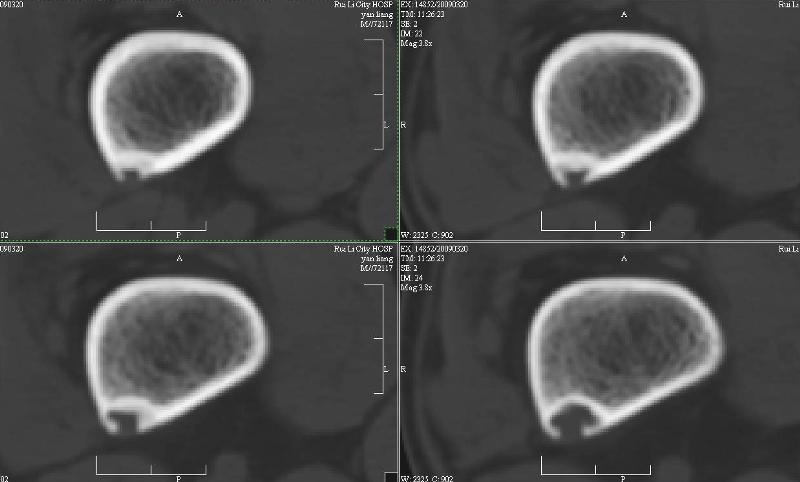

ct:右侧股骨下段后份局限性骨质破坏并病灶区细点状高密度影,性质?骨tb可能性大,软骨瘤、纤维骨皮质缺损及其它待除外,建议结合临床及相关检查考虑。 2、右膝关节腔少量积液。